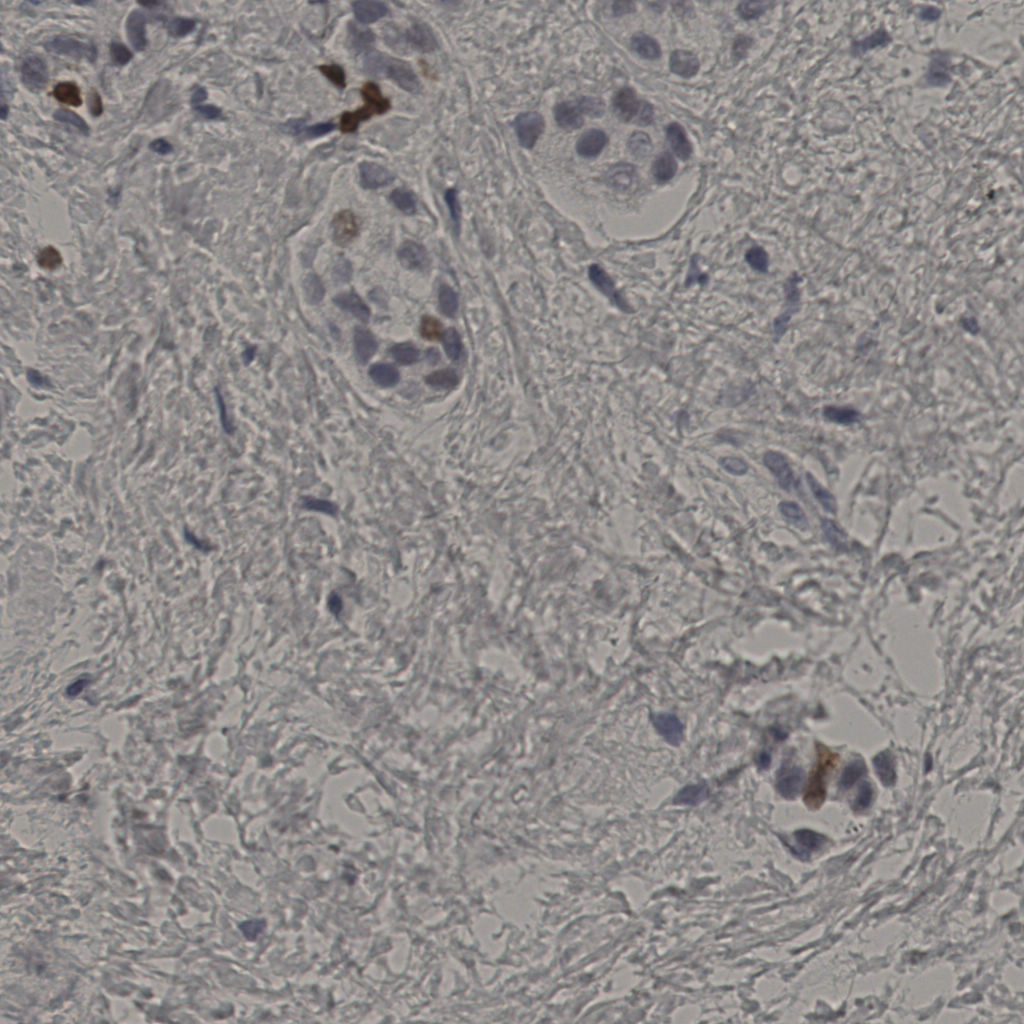

5.31%

Ki67 指数

阴 19502

阳 1093